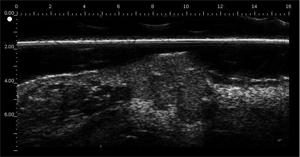

Melanomas Ecografía

Hipoecoica , con ecos de baja densidad. El eco de entrada no está muy marcado o ausente (ausencia de queratosis, ulceración) Melanoma ulcerado en el antebrazo (grosor medido a 3,68 mm en ecografía, grosor histológico). Lesión que infiltra la dermis. Melanoma en la oreja Carcinoma de células basalesCarcinoma de células basales en la frente (por encima de la arteria temporal)Carcinoma de células basales en la cara por encima del mastoidesCarcinomasuperficialCarcinoma pigmentado Nevo dérmico Lesión hipoecoica con muchos ecos, borde con la dermis adyacente mal definidoHistiocitofibroma  Lesión hipoecoica , pobremente limitada con muchos ecos.